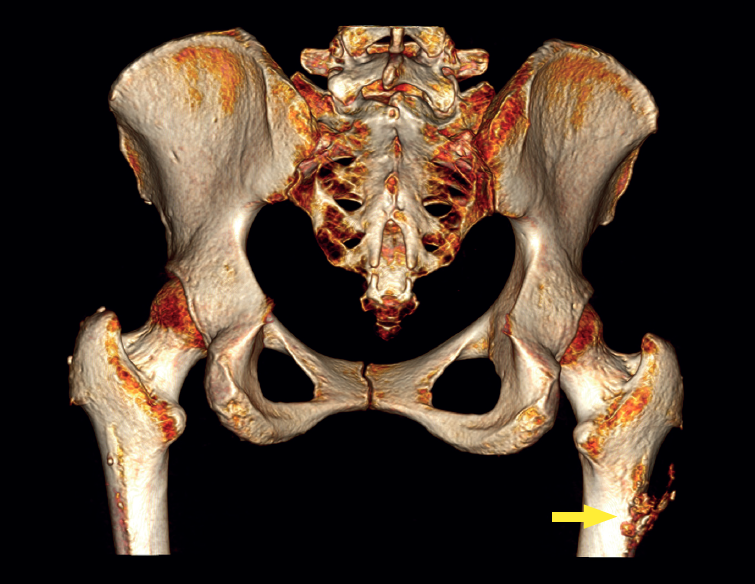

reacae.31181.fs2402007en-figure1.png

The physical examination revealed a limp-free gait and complete joint balance, with no positive signs of femoroacetabular impingement or inguinal pain. Muscle strength was preserved and similar to that of the contralateral side. She experienced intense pain on palpation of the insertion of the gluteus maximus, referred proximally to the ipsilateral buttock. The pain was reproduced on extension against resistance, and prevented sitting for long periods. Plain radiographic and computed tomography (CT) images revealed calcific tendinosis affecting the aponeurotic prolongation of the gluteus maximus in proximity to its insertion in the upper region of the linea aspera of the femur  (Figures 1 and 2) Magnetic resonance imaging (MRI) of the hip showed a labral tear, that proved asymptomatic in the physical examination. In view of the clinical picture of radicular pain, an MRI scan of the lumbar spine and subgluteal space was also performed, ruling out radicular involvement or sciatic neuritis. Her previous treatment over the three years of evolution of the disorder included oral nonsteroidal anti-inflammatory drugs, a specific physiotherapy programme and several ultrasound-guided corticosteroid injections with positive results - though a last session showed no response. Due to the severity and chronicity of the symptoms and their resistance to conservative treatment, surgery was decided to clean and remove the intratendon calcification endoscopically.

reacae.31181.fs2402007en-figure2.png